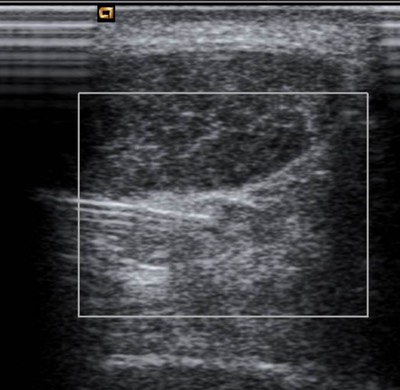

Ultrasound-guided Injections

For accuracy most soft-tissue injections are performed using Ultrasound to guide the needle to the correct position. Examples include:-